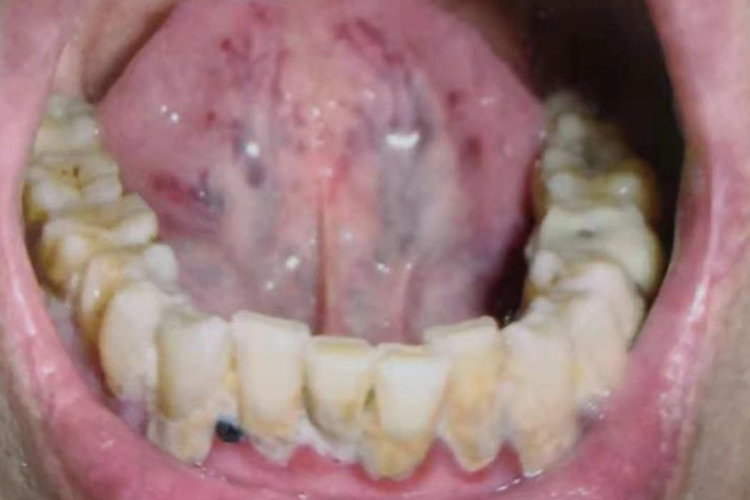

舌头底下有淤血点表现为舌下静脉分支末端增粗,微血管模糊不清,同时,舌系带两侧可见颜色暗红、紫红、暗紫、浅紫,或紫黑色的如大小不等的平坦或隆起的斑点。